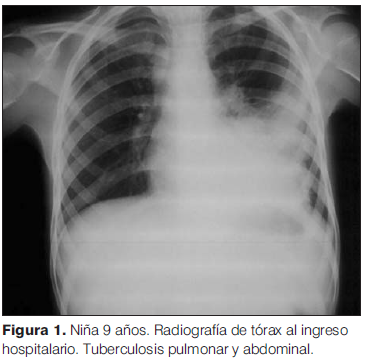

Comenzó 24 horas previas con tos seca, agregó fiebre de hasta 39,5ºC y dolor abdominal difuso a predominio de hemiabdomen inferior. En el momento de la consulta (22 de setiembre de 2010) se encontraba con buen estado general, febril, hemodinámicamente estable, sin síndrome funcional respiratorio. A la auscultación pleuropulmonar se evidenció hipoventilación en cara axilar de hemitórax izquierdo. De los exámenes complementarios al ingreso se destacaban: radiografía de tórax con foco de consolidación paracardíaco izquierdo, con fondo de saco libre (figura 1). El hemograma evidenció glóbulos blancos: 15.500/uL, hemoglobina: 9,8 g/dL, volumen corpuscular medio: 71,6 fL, hemoglobina corpuscular media: 23 pg, plaquetas: 653000/uL. proteína C reactiva (PCR) 112. El hemocultivo fue sin desarrollo. Se diagnosticó neumonía adquirida en la comunidad (NAC) en hemitórax izquierdo, de probable etiología bacteriana inespecífica y como agente etiológico más probable se planteó S. pneumoniae. Se inició tratamiento con penicilina.

Ante la persistencia del dolor abdominal se solicitó una ecografía que mostró múltiples adenomegalias abdominales de hasta 25 mm de diámetro, que impresionaban corresponder al territorio mesentérico y retroperitoneal medio. Se realizó una tomografía computada (TC) de tórax, abdomen y pelvis, en la que se observó, en el lóbulo inferior izquierdo, una extensa área de consolidación parenquimatosa, con escaso broncograma áereo y varias imágenes hipodensas, con adenomegalias hiliares izquierdas, subcarinales, en el receso pleura-ácigo-esofágico y látero-traqueales derechas altas y bajas (figura 2). Se identificaron múltiples adenomegalias mesentéricas, con realce periférico y centro hipodenso, aspecto compatible con necrosis (figura 3). El resto del estudio no mostró alteraciones.

A los 20 días de iniciado tratamiento antituberculoso, se recibió el resultado del cultivo de expectoración, que desarrolló M tuberculosis, confirmando la enfermedad tuberculosa. La paciente culminó el tratamiento antituberculoso en forma completa, con buena tolerancia. Luego del alta fue controlada con radiografía de tórax (figura 4), que evidenció resolución radiológica parcial de la afectación pulmonar.